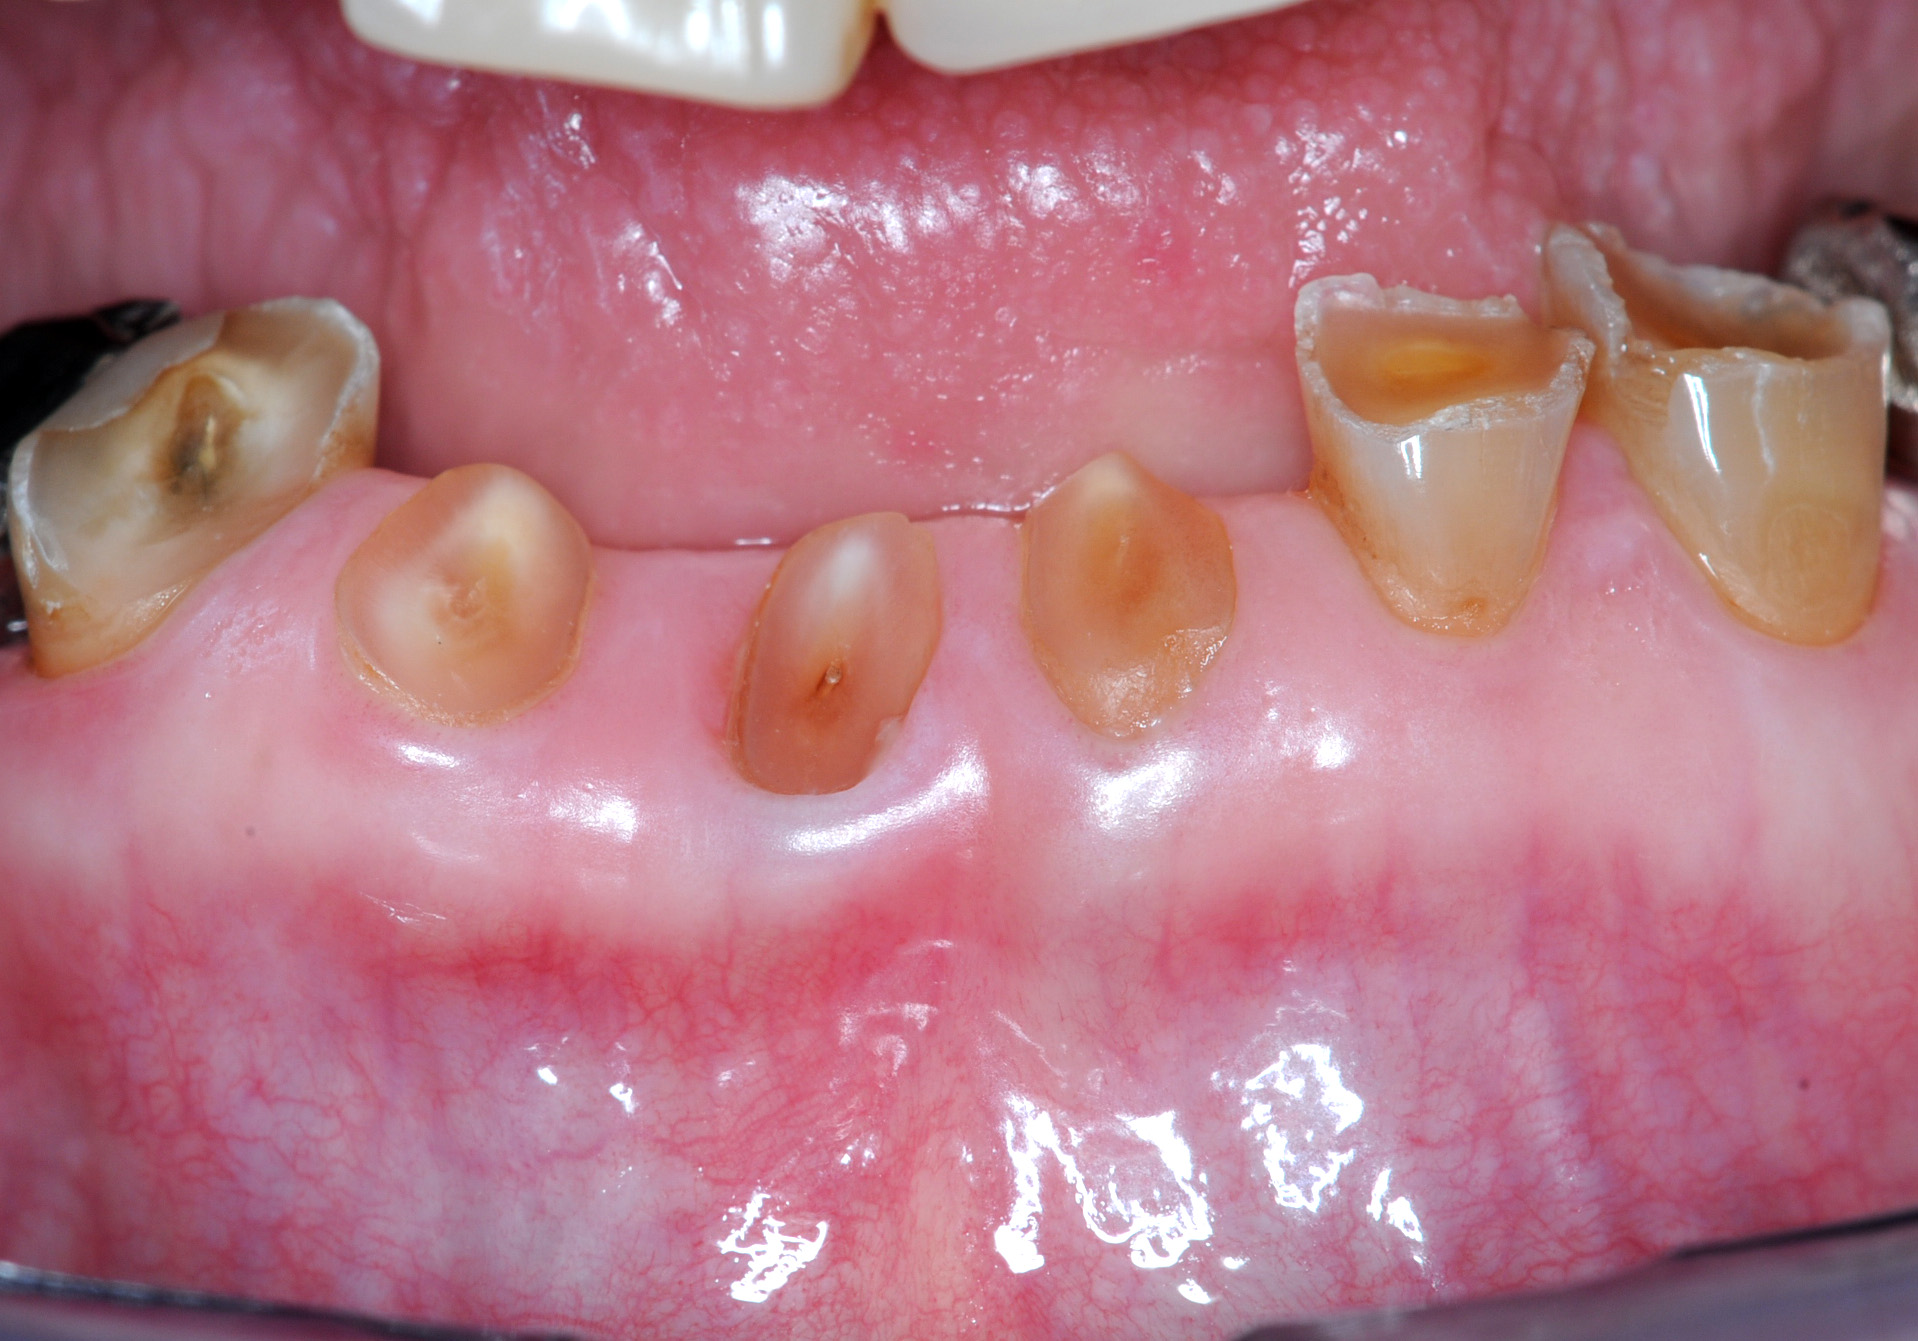

■症例1−1 酸蝕症 Acid Erosion(酢・ポン酢・ビール・焼酎)

全顎に渡り、唇側は酸蝕のためEnamel質が薄くなり、歯頸部付近では象牙質まで露出。Plaque Controlが悪いため、特徴的な歯頸部に表在性のう蝕と着色が診られる。咬合高径が小さいため、義歯の設計が極めて困難である。当然Under

Cutもほとんどなくなっている

患者:69歳、男性

高血圧にてコニール服用中(130/80mmHg)。HEAVY DRINKER(毎日ビール2〜3本、焼酎)。GOT(58IU/l),γ−GTP(174IU/l),高尿酸値(7.3m/dl)。高血圧予防として禁酒は出来ないため、減塩目的で長年醤油の代わりにポン酢や酢を多用していた。その結果、重度酸蝕症に罹患。さらにビール(pH4)と焼酎(pH5)が拍車をかけた。成人男性にしては極めて小さい歯牙形態に陥ってしまった。